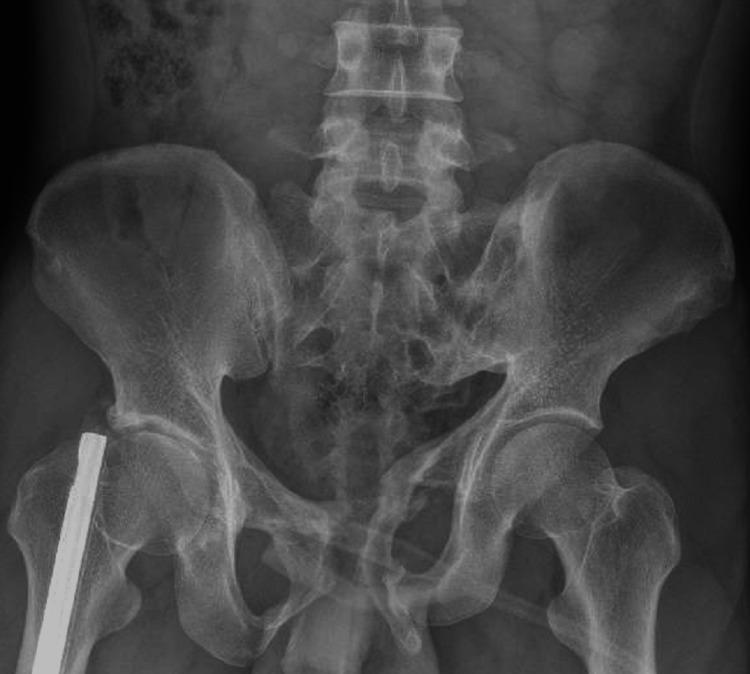

Pelvic fracture is one of the common causes of erectile dysfunction (ED). The pathophysiology of ED following pelvic injury is quite complicated and comprises vascular, neurogenic, corporal, as well as psychogenic causes. Penile prosthesis implantation is the third-line treatment of ED due to any reason including pelvic trauma that poorly responds to other standard treatments. In this study, we reported a case of a 33-year-old man with severe erectile dysfunction and urethral stricture following a complex pelvic fracture due to a traffic accident who was successfully implanted with a three-piece inflatable penile prosthesis at People's Hospital 115. At the sixth month of follow-up, this device has been working effectively, the patient had the ability to attain full erection for sexual intercourse. Both the patient and the partner are satisfied with their sexual lives. ED is a long-term consequence of pelvic fracture. The high proportion of young patients with a demand for erection rehabilitation and complex pathophysiology make the treatments even more challenging. Penile implant surgery is a potential treatment for refractory ED patients suffering from pelvic trauma.